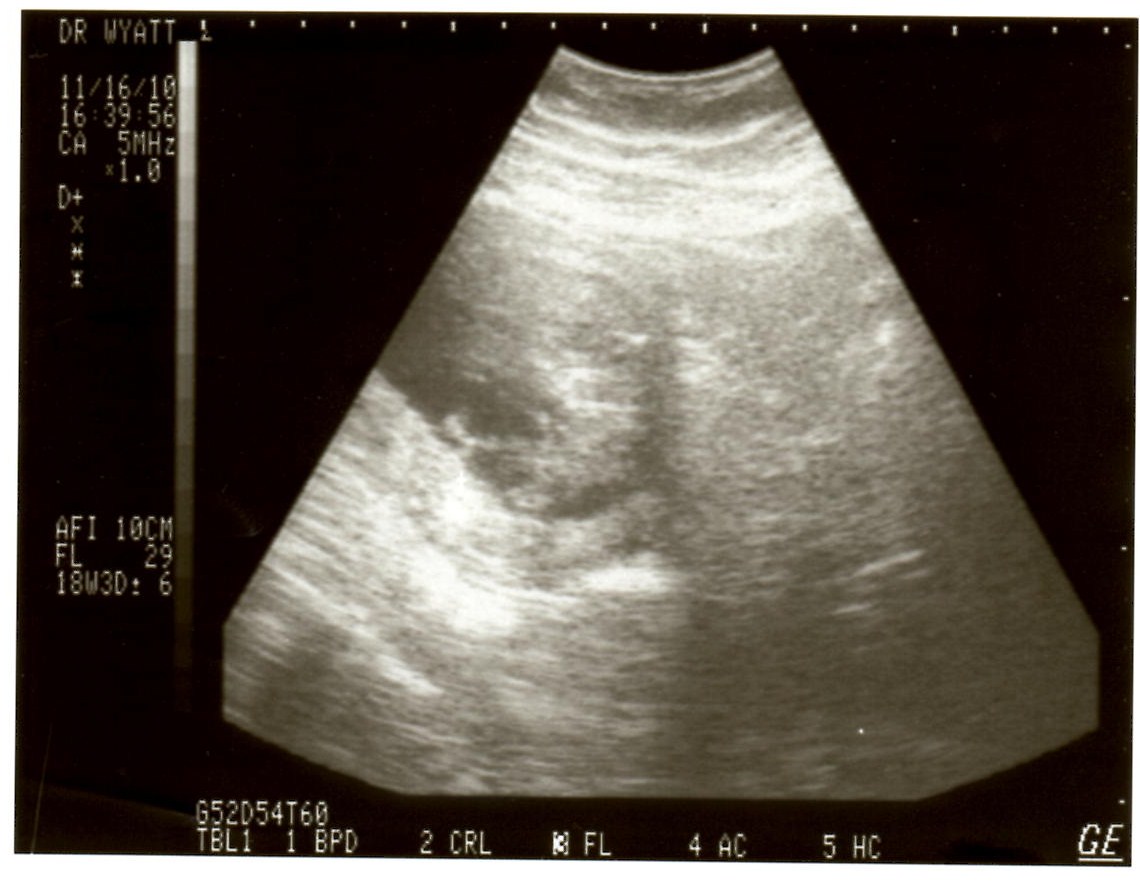

Mahina’s second ultrasound November 16, 2010